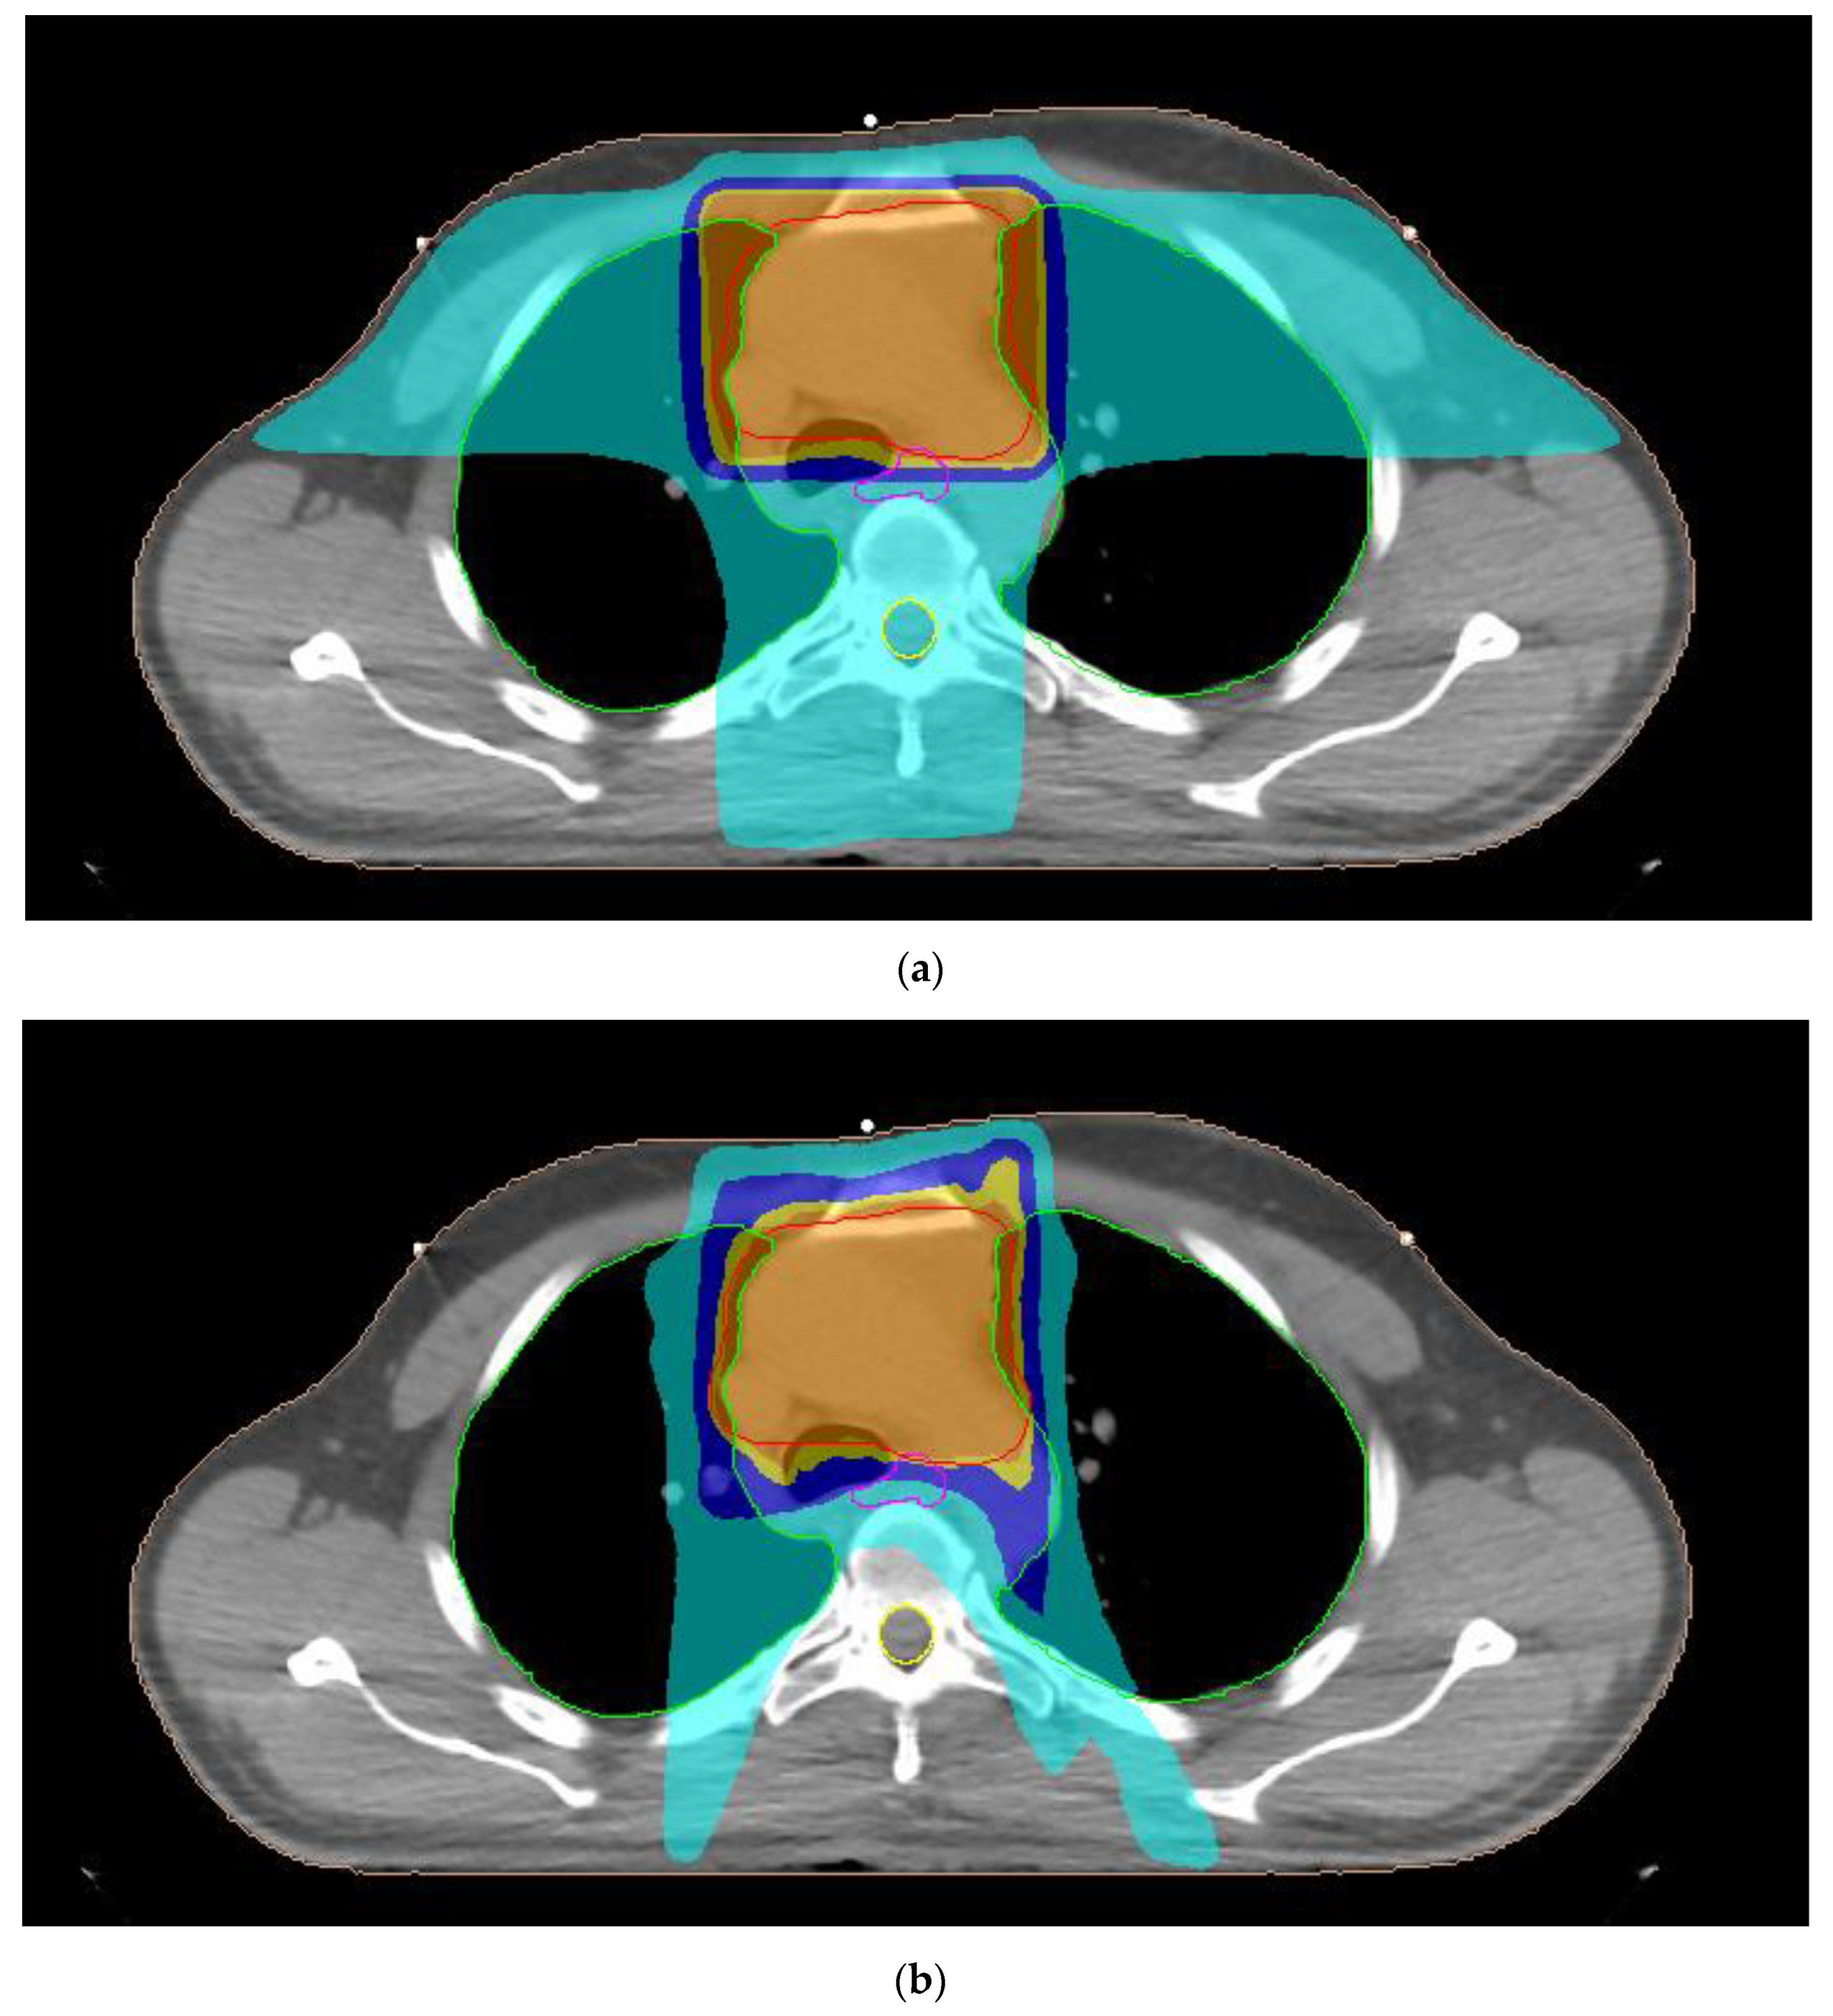

2.2. Treatment Planning